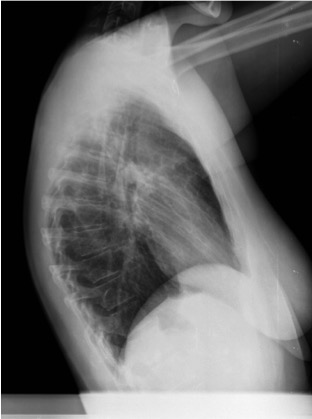

- En un principio podríamos decir que existe un aumento de densidad retrocardiaco que podría ser compatible con condensación neumónica a dicho nivel, sin embargo estamos ante una placa poco inspirada, lo cual puede llevarnos a cometer errores diagnósticos.

- Se recomendó volver a realizar la radiografía, observar a continuación:

Ya no se observa el aumento de densidad retrocardiaco, la placa es normal.

INSPIRACIÓN: Una placa bien inspirada es aquella en la que se observar 6-7 arcos costales anteriores o 10-11 arcos costales posteriores. Lo contrario puede producir imágenes falsas de condensaciones o de seudocardiomegalia.